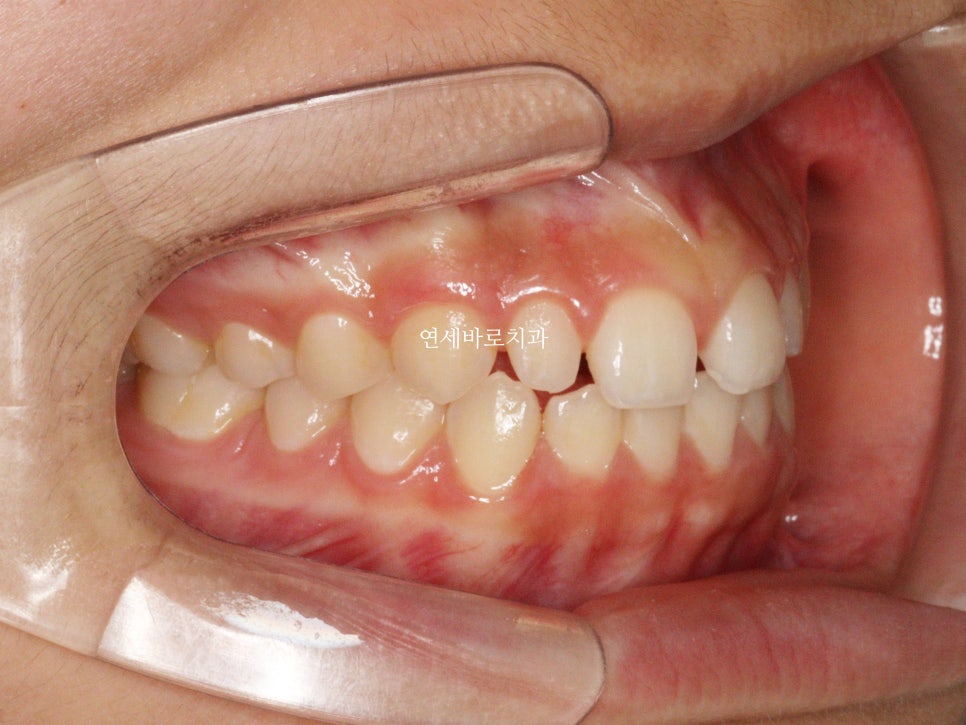

1월에 왔던 아이입니다. 어금니 교합은 너무나 좋아서 건들일것이 없었어요

앞니만 부분교정으로도 충분했습니다.

처음 치료를 시작한 날의 모습입니다.